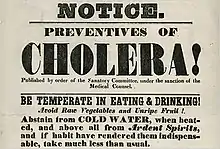

Emperor Pedro II of Brazil visiting people with cholera in 1855. Hand bill from the New York City Board of Health, 1832—the outdated public health advice demonstrates the lack of understanding of the disease and its causative factors.

Hand bill from the New York City Board of Health, 1832—the outdated public health advice demonstrates the lack of understanding of the disease and its causative factors.